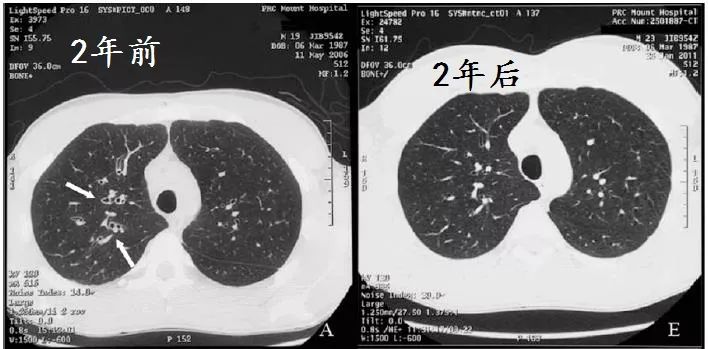

He adhered to treatment and significant improvement in symptoms was noted over 6

months. At a review 2 years later, he had complete resolution of symptoms and further improvement in spirometry values , and repeat high-resolution computed tomography showed no evidence of previously noted dilated airways.

病人坚持治疗,6月后症状好转,2年后,各方面都好转,连支气管扩张都好了!

This case highlights the fact that not all radiological postinfective bronchiectatic changes should be considered as irreversible.Early effective therapy should be provided and the patient monitored for resolution。

事实胜于雄辩,影像学发现的支扩,并不都是不可逆的。早期治疗,随访,有希望缓解。

下面是作者提供的精彩图谱,什么时候,国内的文献也有图,有稍微清晰一点的图。